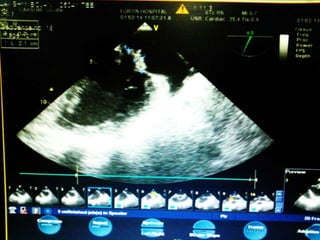

• On 29th Jan Screening Echo was done which

showed IHD , RWMA +, Myxomatous MV,

dIlated LA, moderae MR, Grade 1 AR,

moderate TR, Severe PAH (PASP 62mmHg), EF

50%, no clots /vegetations.

• On 29thJan Screening Echo was done which showed IHD , RWMA +, Myxomatous MV, dIlated LA, moderae MR, Grade 1 AR, moderate TR, Severe PAH (PASP 62mmHg), EF 50%, no clots /vegetations. • On 31st Jan, Lasix infusion was started and diuresis done , patient was put on NIV.